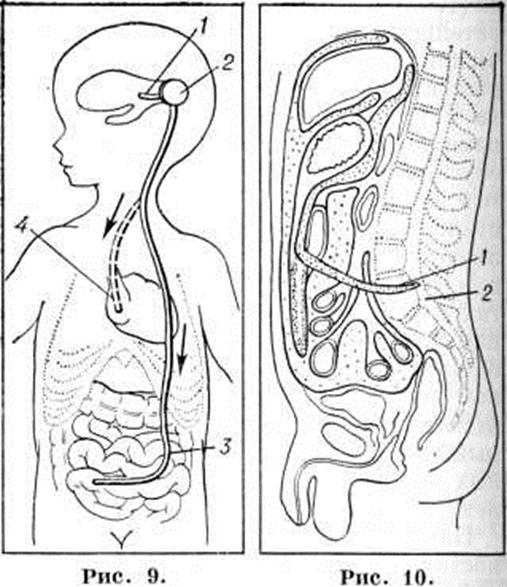

Вентрикулоаурикулярное шунтирование — постоянное отведение жидкости из бокового желудочка мозга в правое предсердие (рисунок 9), проводят с помощью дренажной системы с клапаном Шпитца — Хольтера или Пуденца — Хейера. Предпочтение отдаётся системе Пуденца — Хейера, при которой клапан помещается на сердечном конце катетера. Клапан препятствует забросу крови в дренажную трубку и желудочки головного мозга.

Вентрикулоперитонеальное шунтирование — отведение жидкости из бокового желудочка в брюшную полость (рисунок 9). Операция показана в основном для лечения Гидроцефалия у детей раннего возраста. Используют дренажную систему с клапаном, который помещается на конце вводимого в брюшную полость катетера.